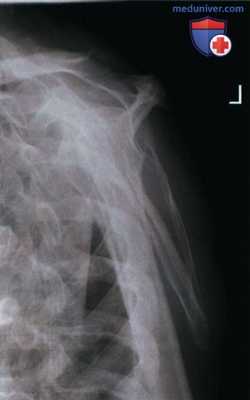

РИСУНОК 3 Рентгенограмма лопатки в ПЗ проекции без отведения плеча. РИСУНОК 4 Рентгенограмма лопатки в ПЗ проекции с недостаточной ретракцией плечевого сустава. РИСУНОК 5 Рентгенограмма лопатки в ПЗ проекции: перелом.

а) Анализ. Нижнелатеральный край лопатки накладывается на грудную полость, верхний угол лопатки накладывается на ключицу. Плечевая кость была отведена недостаточно.

б) Коррекция. Отведите плечевую кость на 90° относительно туловища.